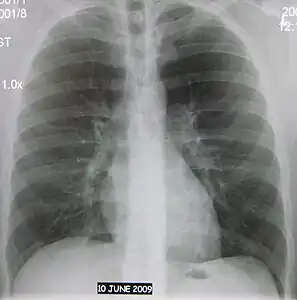

Normal AP CXR

AP CXR showing right lower lobe pneumonia